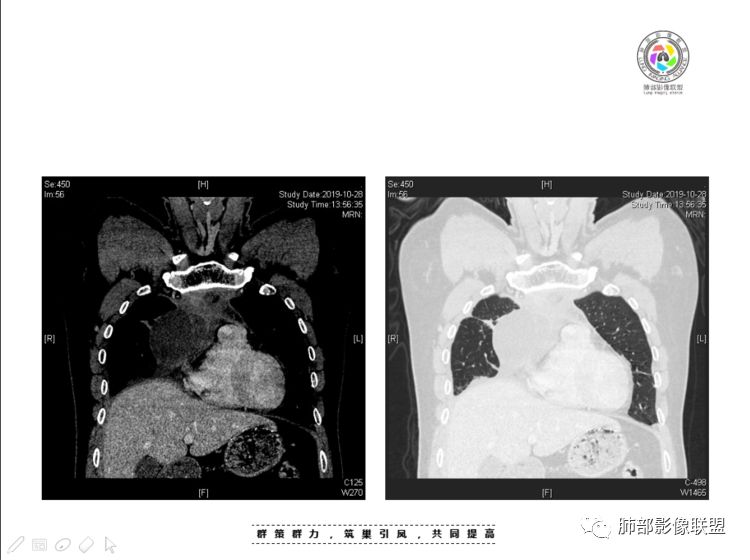

南边:大家看看前纵隔的病灶,符合肿瘤吗脂肪,周围密度增高

三个石头:比较散;像炎症的蔓延生长南边:是,这些看着心里不踏实觉得把这个纳入肿瘤去考虑是否合适总觉得边缘收缩的、散在的朝周围蔓延;中央还跨过脂肪,朝对侧胸膜蔓延把这个与囊性病变连到一起去考虑是否还需要斟酌一下因为这个就方向差异大了南边:连在一起,囊实性,边界不清,自然考虑恶性:如果独立,囊张力高、边界清楚,间隔,自然朝良性考虑:

我认为囊张力高,积液中的气体均在周围,外侧、下方,囊内有间隔:各腔密度不一致;提示:囊腔属于前纵隔,不是包裹性积液;现在的问题:囊腔与内侧的病灶是否是一体的

南边:我总觉得这个纵隔内不像是一个肿块的改变,扁平,周围蔓延:有符合炎性的的特点,或者肿瘤的侵犯;但是肿瘤的侵犯,不大符合,实性部位的边缘过于柔和,没有毛糙的侵犯边缘。

2、前纵隔内病灶囊实性混杂密度病灶,囊性病灶主要位于右侧,张力较高,有分隔影,囊壁右侧缘光整,病灶左侧实性部分边界不清明显强化,病灶肺瘤交界面大部分边界清楚,部分模糊。

前纵隔肿块伴囊变坏死常见以有胸腺瘤、胸腺癌、淋巴瘤和生殖细胞肿瘤。

纵隔内病灶不符合肺癌转移途径,且纵隔内单发的囊实性转移罕见。淋巴瘤无论是分布、形态、密度、还是强化方式度不符合。

胸腺瘤/胸腺癌符合吗?

胸腺瘤/胸腺癌:病灶内那么大的囊,常规考虑B型以上胸腺瘤,囊内有分隔影,病灶周围脂肪间隙模糊,常规考虑侵袭性胸腺瘤或胸腺癌,若侵袭性胸腺瘤,常侵犯胸膜、心包,很少累及肺。胸腺癌易侵犯胸膜、肺并纵隔淋巴结及远处转移。但肺内腺癌形态更符合原发灶。胸膜及叶间裂转移则即可来自肺,也可来自胸腺癌。

尽管前纵隔病灶缺乏相关病理资料,但是小编还是认为肺内与纵隔病灶以二元论解释。只是肺内恶性病灶引发的胸膜改变可能会影响我们对纵隔病灶的判断。